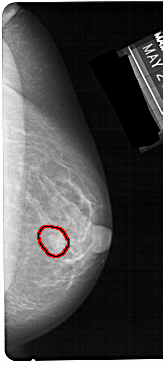

A_1304_1.RIGHT_MLO

FILE: A_1304_1.RIGHT_MLO.OVERLAY

TOTAL_ABNORMALITIES 1

ABNORMALITY 1

LESION_TYPE MASS SHAPE OVAL MARGINS CIRCUMSCRIBED

ASSESSMENT 4

SUBTLETY 4

PATHOLOGY BENIGN

TOTAL_OUTLINES 1

BOUNDARY